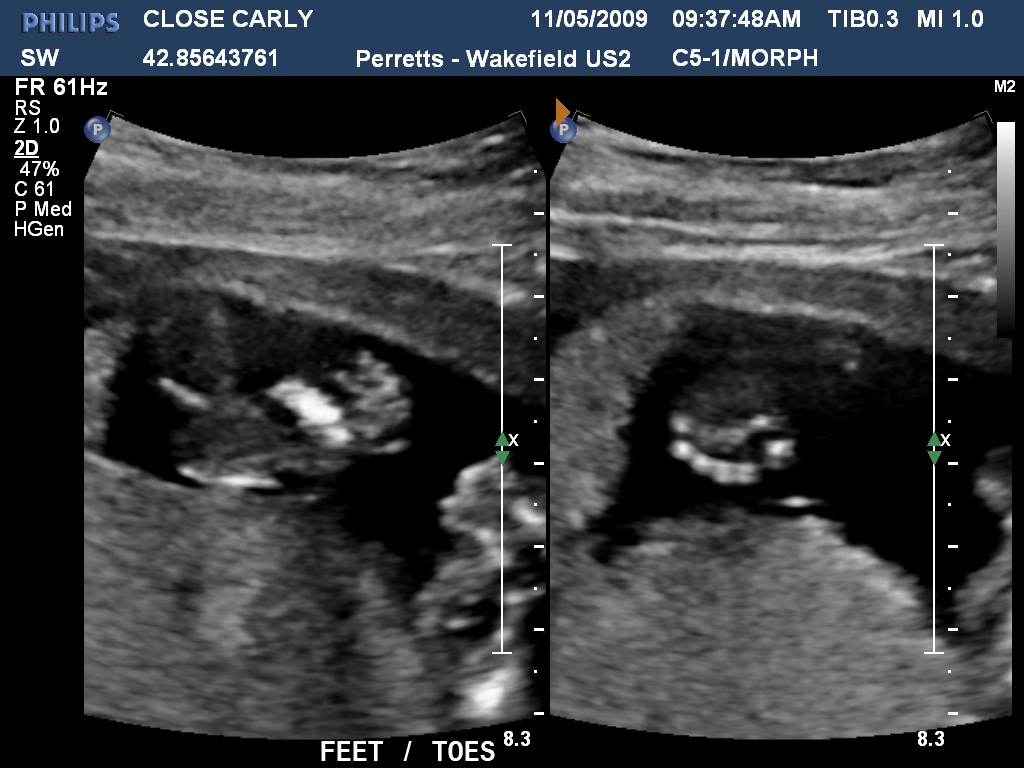

Wow how time flies! Carly is now 159weeks pregnant and now definately showing. Last week we had the first real scan and got to see hands and feet, the bub was quite active and gave the radiologist a hard time! Below are a few photos of both the bub and the expectant Mum to be!